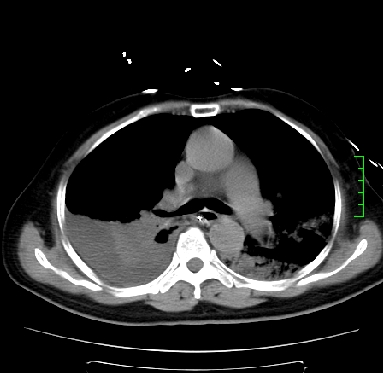

icu病人,几天都没明确诊断。m,76y,咳嗽、咳痰1周,伴气促,右胸痛入院,pe:t38.3c p135 r25 bp135/85。双肺可闻及大量湿罗音,心、腹未见明显异常。诊断:1心衰?2肺部感染?3冠心病?

9号平片

11号ct

双肺感染性病变,下叶膨胀不全,胸水,左室大。

1)两肺感染性病变(右肺下叶肺脓肿可能)。2)双侧胸腔积液,以右侧为甚。

ards,肺感染性病变,右下叶实变,双侧胸腔积液,右侧为著,叶间胸膜积液,右上肺陈旧性tb纤维灶,左室大。